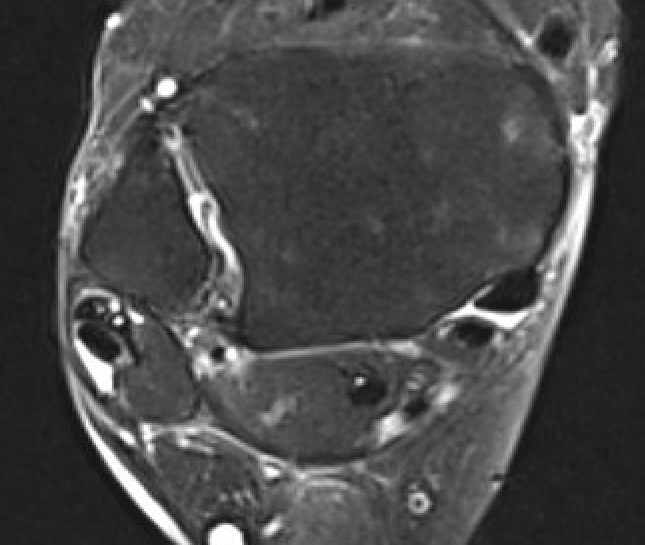

Findings

- tendonitis - fluid around tendons

- tendinopathy - tendon thickening

- tears

Avoid magic angle effect at ankle - parasagittal obliques / plantar flex ankle

Tendinitis - fluid around tendon

Tendinopathy - thickened PL

Peroneal brevis tears